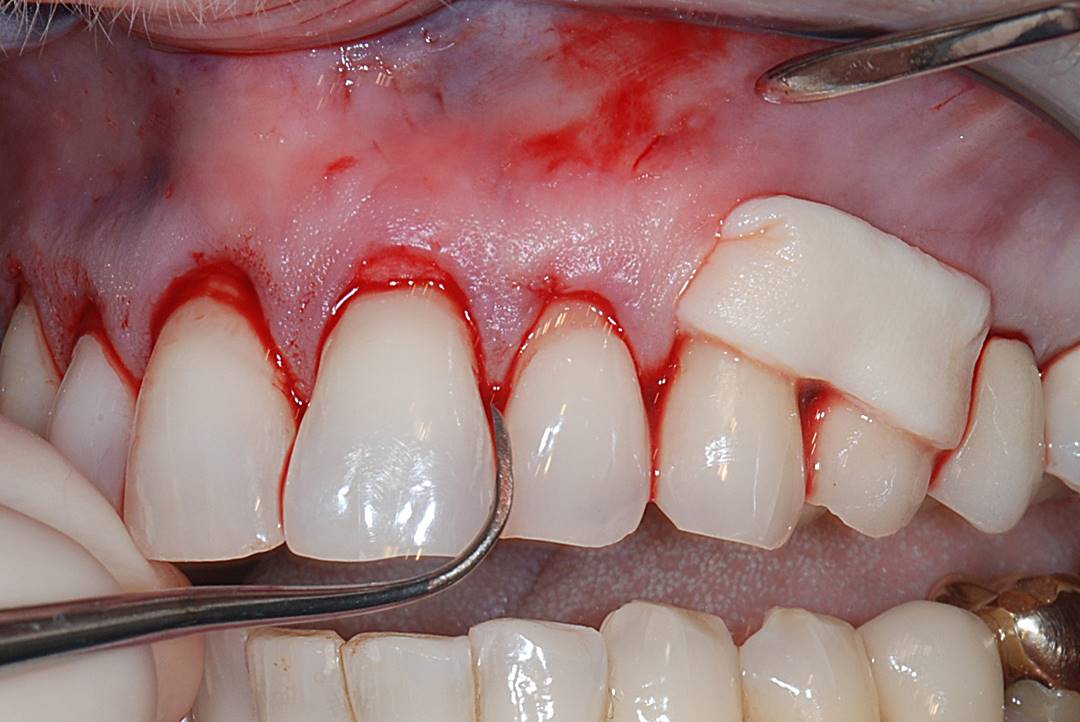

A patient presented with moderate recession requiring root coverage and increased thickness of the alveolar housing (Figure 9). A series of parallel incisions was completed using instruments made specifically for microsurgery; these incisions were performed utilizing high magnification (ie, 5.5 magnification via loupes). The distance between the incisions was roughly the amount of root coverage necessary on the adjacent teeth (Figure 10).25

The isthmus of tissue between the parallel incisions was removed. A split-thickness flap was elevated leaving connective tissue on the bone and providing access for root preparation.

To ensure a smooth root surface, rotary instruments with finishing burs and curettes are used. A glycine air-polishing unit (eg, Air-Flow Master, Hu-Friedy, hu-friedy.com) was used to impart the final smoothing of the roots and remove the smear layer and biofilm.